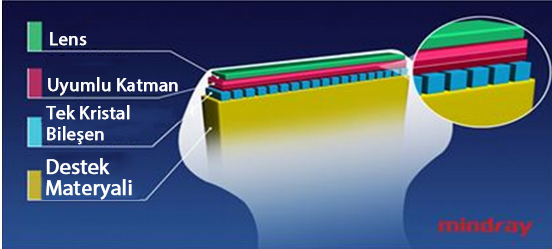

Single Crystal ile 3T Prob Teknolojisi Tek Kristalli

Daha belirgin g?rĂŒntĂŒler sa?layan, M9 ile uyumlu tĂŒm problar Mindray'in benzersiz 3T prob teknolojisiyle teslim edilir. Single crystal teknolojisinin eklenmesiyle gĂŒcĂŒ artan M9, ?zellikle zorlu hasta taramas? s?ras?nda daha iyi penetrasyon ve dinamik renk ak??? olana?? sunar.